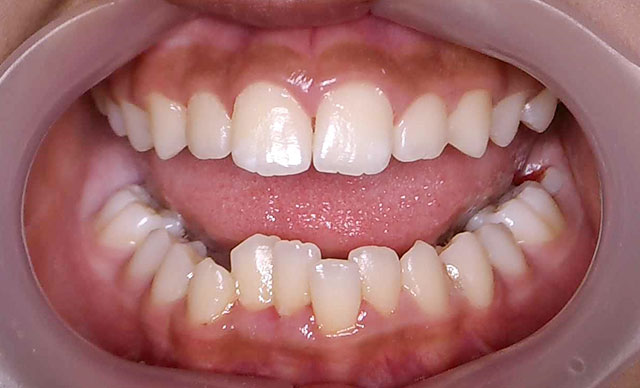

- case.8

術前

術後

症状:すきっぱ治療期間約4ヶ月